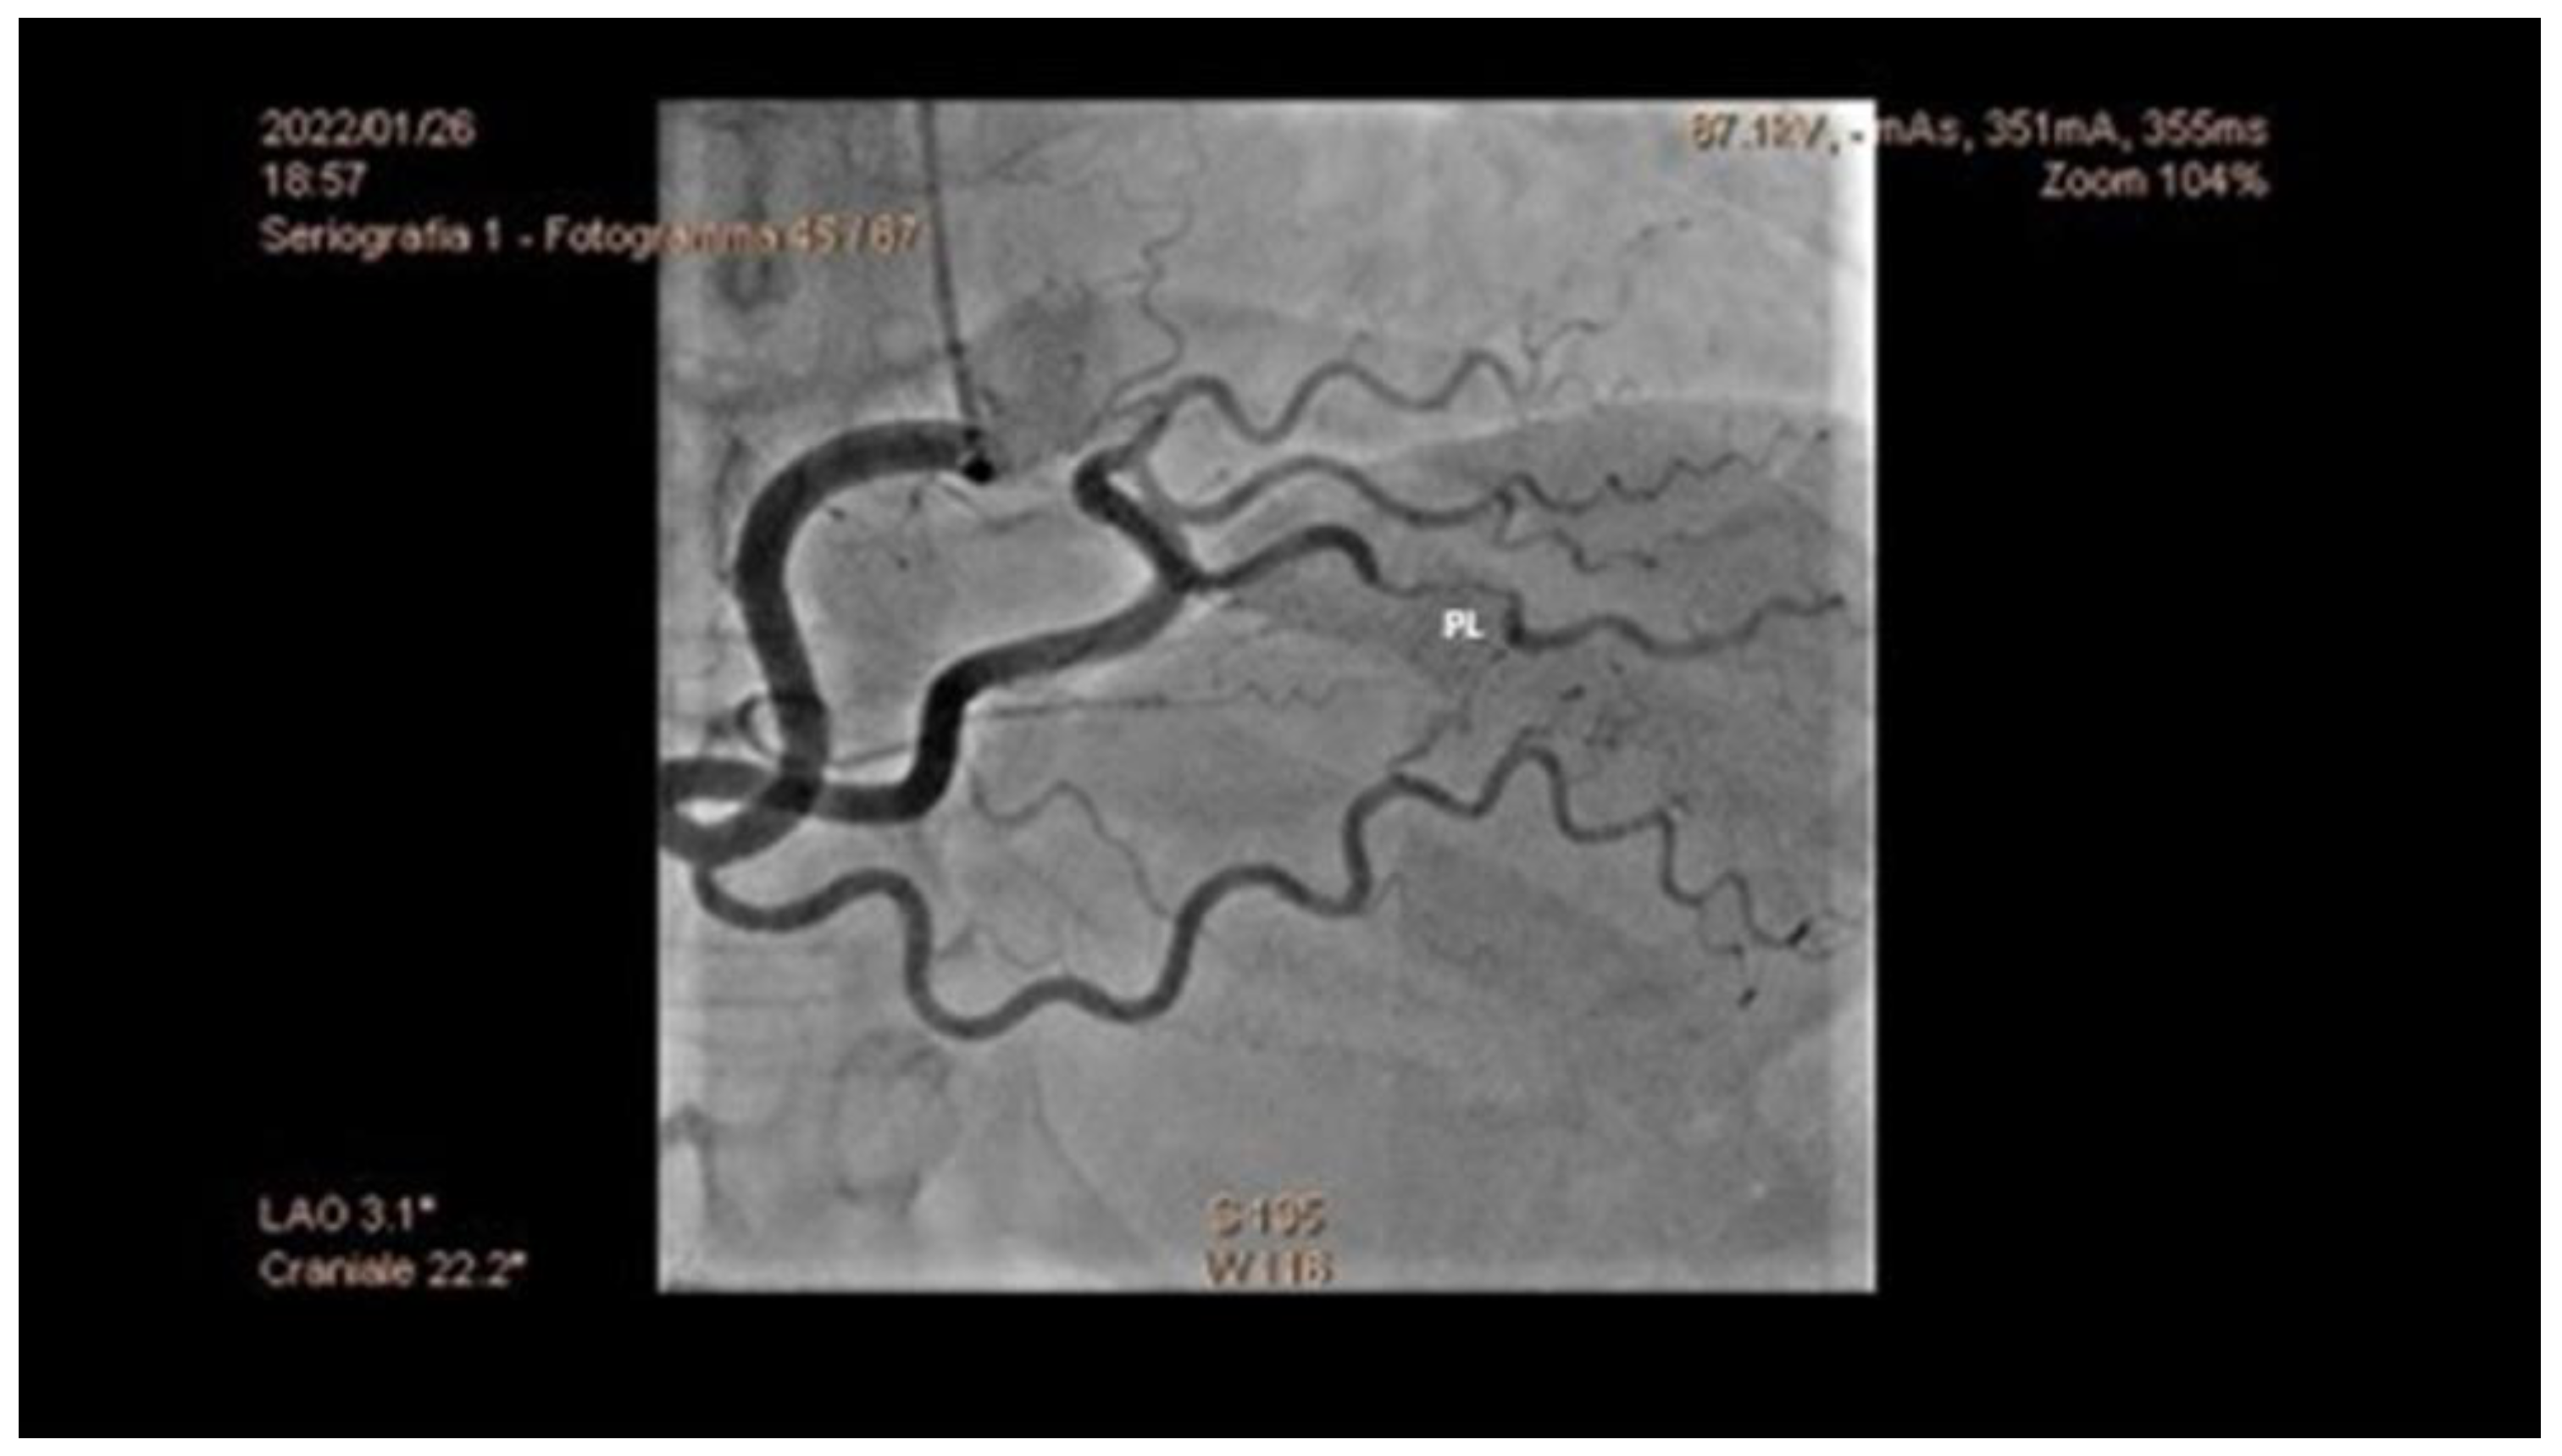

5.1. Angiography

- Increased coronary tortuosity;

- Predilection for more distal coronary segments;

- Predominant involvement of the left anterior descending coronary artery;

- False lumen starting and/or ending at a side branch;

- Absence or reduced incidence of co-existent atherosclerosis;

- Association with FMD;

- Association of sites of dissection with myocardial bridging.